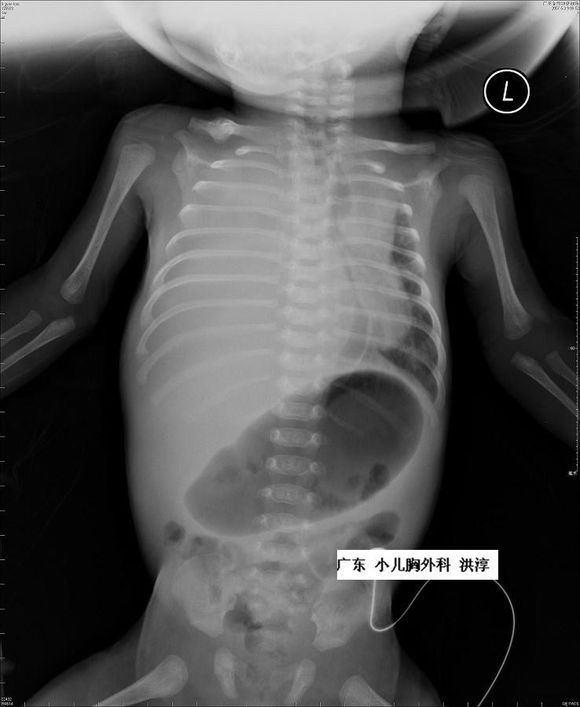

针对胎龄大于32周的胎儿胸腔积液,出生后在建立静脉通路,保证体循环血容量的情况下给予胸腔穿刺并密切视察可能是最好的选择。

对小于32周的FHT胎儿,有3种方式提供选择:胸腔穿刺术、胸腔羊膜腔分流,以及胸腔-母体皮下引流。但应该关注的是,这些操作均有可能出现感染、出血、胎膜早破、早产及损伤胎儿的风险。

胸腔-羊膜腔分流术的胎儿在娩出后需夹闭或拔除引流管避免新生儿气胸的发生。如接受宫内治疗的胎儿胸腔积液仍进行性增多,可考虑在妊娠35 ~ 36 周时终止妊娠,并且在产后进行新生儿胸腔穿刺术提高新生儿的存活率。